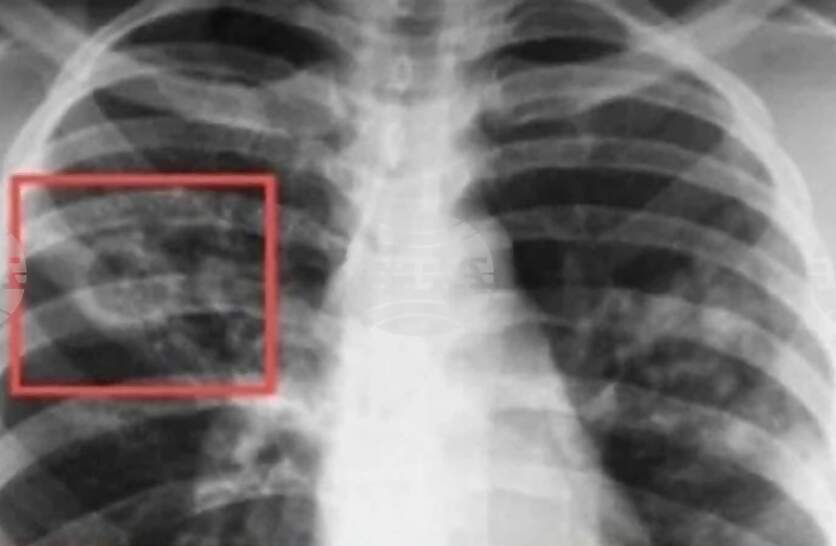

Започва Седмица на отворените врати за туберкулоза. Това съобщават на сайта си от Столичната регионална здравна инспекция (СРЗИ). Днес се отбелязва Световният ден за борба с туберкулозата. Инициативата е в рамките на изпълнението на Националната програма за превенция и контрол на туберкулозата в България, а целта е да се повиши обществената информираност по отношение на заболяването. До 27 март 2026 г., в Кабинета за анонимно, безплатно консултиране и изследване за ХИВ/СПИН (КАБКИС) ще бъдат предоставяни здравно-информационни материали, насочени към превенция на туберкулозата, както и безплатни консултации за начините на предаване на болестта, симптомите, възможностите за профилактика и значението на ранната диагностика. Кабинетът се намира в сградата на СРЗИ - ул. „Враня“ 20, ет. 5, стая 520, посочват от инспекцията. От СРЗИ призовават гражданите да се възползват от предоставените възможности за консултация като част от общите усилия за ограничаване на разпространението на туберкулозата. В България диагностиката, лечението и профилактиката на туберкулозата са безплатни за всички, които се нуждаят, независимо от техния здравноосигурителен статус, посочват на сайта си от Националния център по заразни и паразитни болести. По инициатива на Световната здравна организация, всяка година на 24 март се отбелязва Световният ден за борба с туберкулозата. Това е възможност за повишаване на осведомеността на населението за тежестта на болестта в национален и световен мащаб и за подобряване на усилията за грижа и превенция. Датата е избрана в чест на първото научно съобщение, направено от д-р Робърт Кох, който на 24 март 1882 г. обявява, че е открил причинителя на туберкулозата - бактерията Mycobacterium tuberculosis. Издръжливостта на туберкулозните бактерии във външната среда е много висока, посочват от онлайн платформата "Плюс мен", създадена от Министерството на здравеопазването (МЗ) с цел популяризиране на ваксините и ползите от тях. В жилищни помещения, върху различни предмети запазват инфекциозните си свойства повече от три месеца. Основният начин на предаване на причинителят на туберкулозата е при говор, издишване, кихане, кашляне. Поради високата издържливост на туберкулозните бактерии във външната среда е възможно те да се отделят с храчки, да изсъхват и във вид на вторичен аерозол да бъдат вдишани. В редки случаи причинителят на туберкулозата се предава и при консумация на заразена храна, най-често при консумация на заразено мляко. Министерството на здравеопазването провежда дългогодишна политика по профилактика на туберкулоза. От 1951 г. в страната ни е въведена задължителна ваксинация срещу болестта. Изпълнява се и национална програма за превенция и контрол на туберкулозата, чрез която се осигурява лечение на пациентите и наблюдение и профилактика на техните контактни лица, посочват още от "Плюс мен". През януари 2026 г. на сайта на МЗ за едномесечно обществено обсъждане беше публикуван проектът на Национална програма за превенция на туберкулозата в Република България 2026-2030 г. Във финансовия план към проекта на програмата са предвидени 4 440 100 млн. евро, които ще бъдат осигурени от бюджета на МЗ.